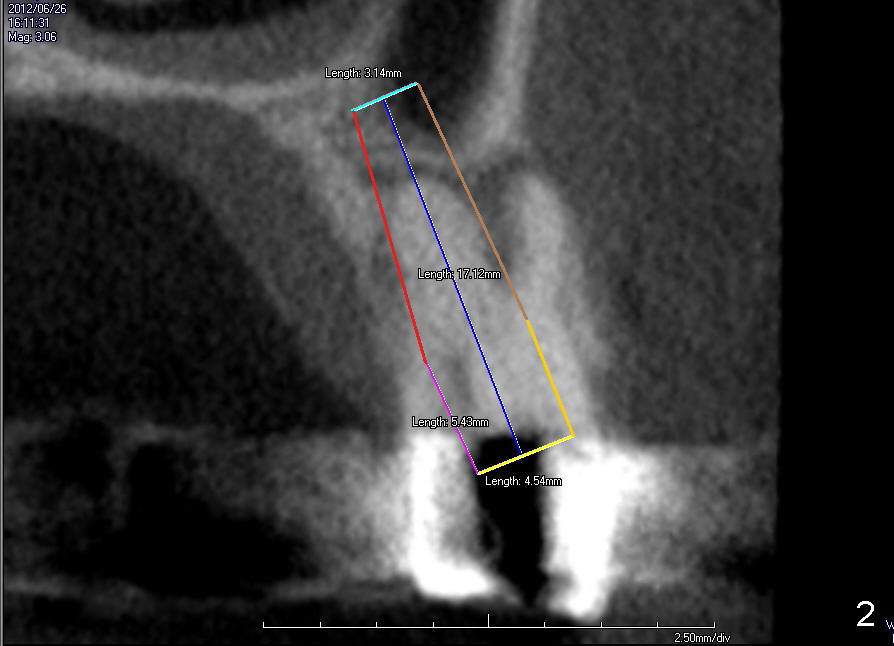

The tooth #13 has broken down to residual root now.  CBCT sagittal (Fig.1,3) and coronal (Fig.2,4) sections show designs of T (4.5x17 mm Fig.1,2) and D2 (Fig.3,4) implants.  Which is better?  It appears that sinus lift with bone graft is expected.